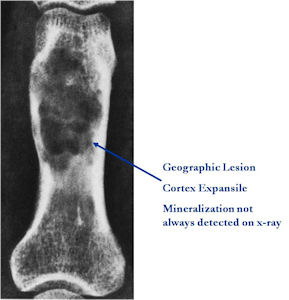

Plain X-rays:

- Geographic, circumscribed lesion usually around 5cm in size.

- There may be expansion of bone, cortical thinning and cortical breakthrough. A soft tissue mass may accompany this lesion but the soft tissue component is usually contained by the periosteum.

- The periosteum remains intact around the soft tissue component. Might need a CT scan to detect the subtle calcification (Egg Shell Rim of Calcification) associated with an intact periosteal reaction

- The lesion may be entirely radiolucent but usually shows some degree of mineralization. Mineralization may appear stippled like cartilage but do not see chondroid pathologically. Mineralization is sometimes better detected on a CT scan rather than an x-ray.

- Usually less surrounding sclerosis than an osteoid osteoma.

- Arise from the Diaphysis (75%) more commonly than Metaphyseal (25%)

- 4 cm to 6 cm in size